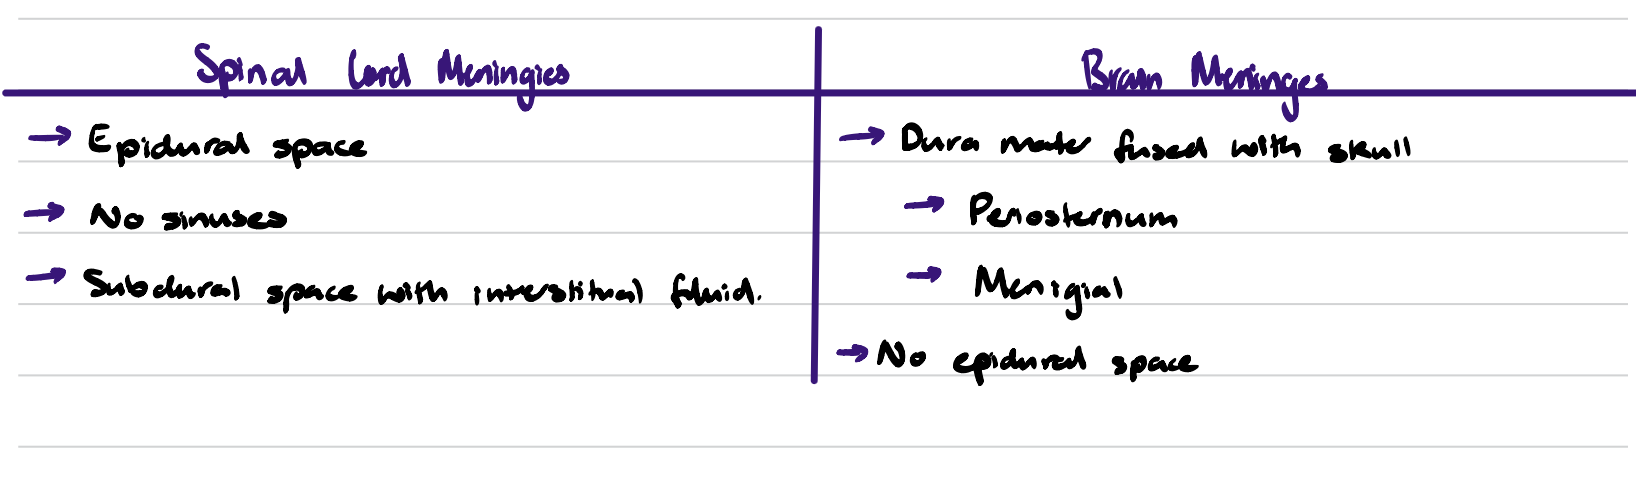

Brain VS Spinal Meninges